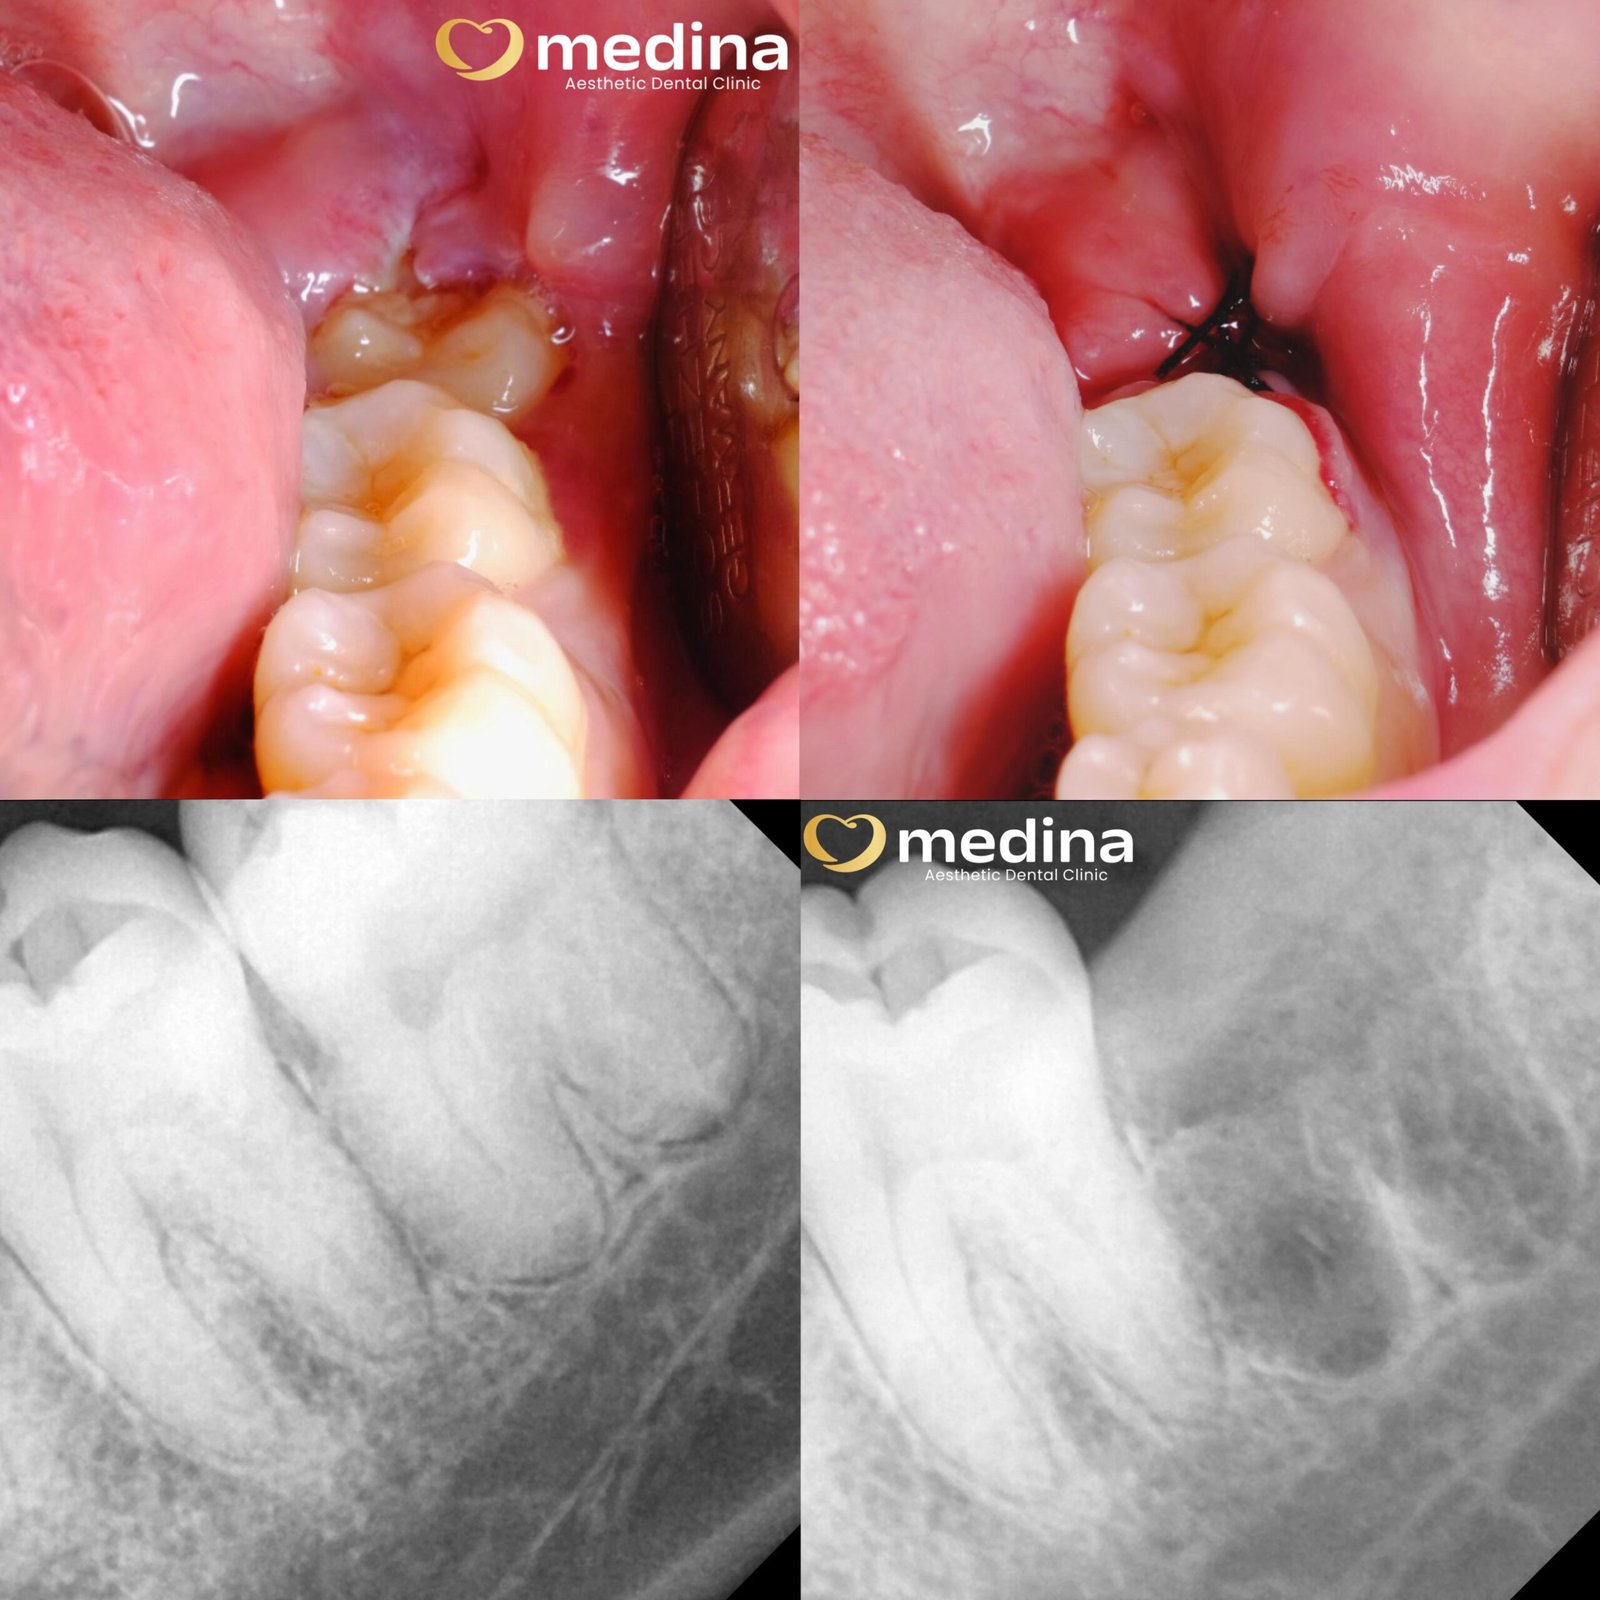

Cabut Gigi Bungsu

adalah pencabutan gigi dengan prosedur bedah mulut tanpa harus opname.